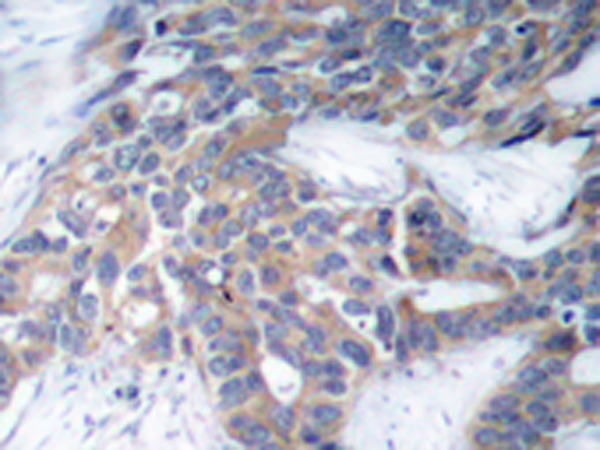

IHC positive control:

Human breast carcinoma

IHC Recommend dilution:

50-100